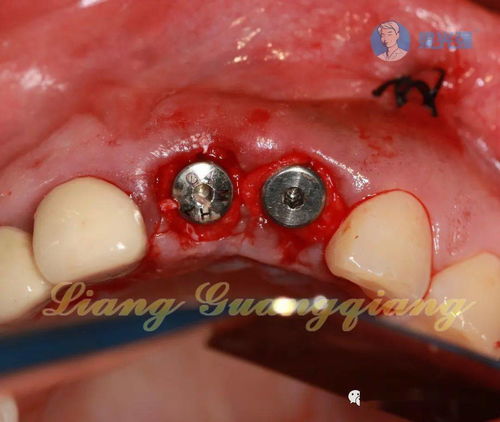

2、做種植牙后24小時(shí)內(nèi),不能刷手術(shù)區(qū)牙齒,以免刺激傷口。注意保持口腔衛(wèi)生,每天早晚堅(jiān)持刷牙一次,飯后用漱口水含漱數(shù)次,防止傷口感染。

3、做種植牙后減少手術(shù)區(qū)周?chē)∪獾倪\(yùn)動(dòng),手術(shù)后的三個(gè)月內(nèi)盡量不要大笑、頻繁講話等,以防腮部過(guò)分運(yùn)動(dòng)而出現(xiàn)傷口撕裂。

4、經(jīng)常觀察種植體及創(chuàng)口的情況,一旦發(fā)現(xiàn)問(wèn)題,及時(shí)向醫(yī)生反映,盡快解決。

5、種植牙手術(shù)后當(dāng)天,應(yīng)吃半流或全流食,拆線以前進(jìn)軟食,不使用手術(shù)區(qū)的牙咀嚼食物。拔牙后即刻種牙的患者,術(shù)后三個(gè)月內(nèi)不宜用種植牙咀嚼過(guò)硬食物,要戒煙酒及刺激性食物。